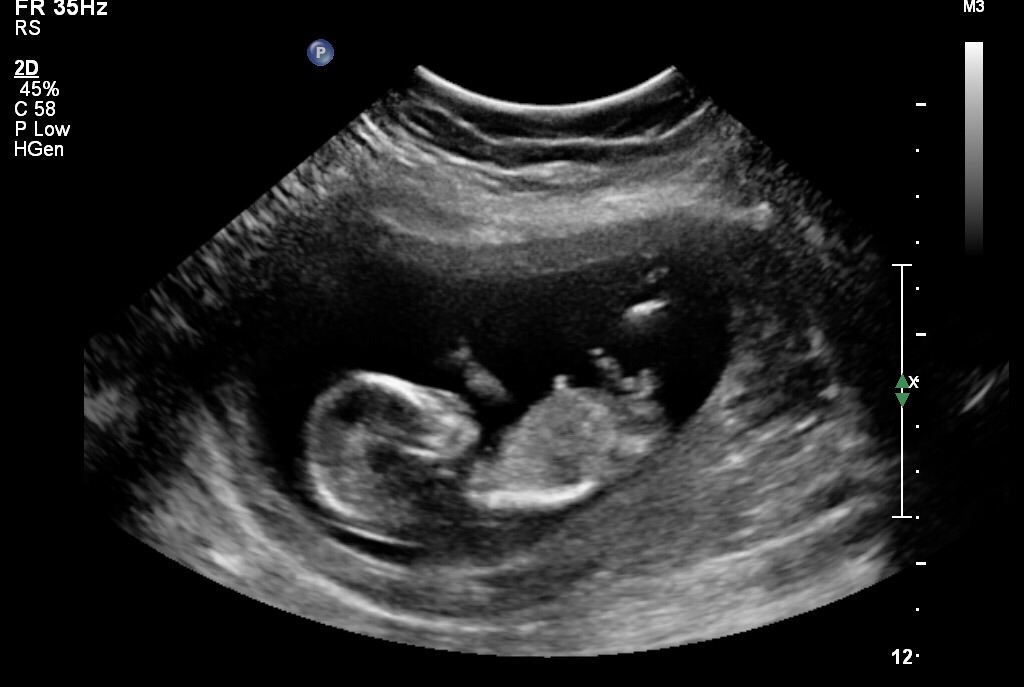

Was hoping for a better pic so not sure what part is the nub can anyone help me please Attachment 34197Attachment 34198

I would guess boy

I would guess BOY too because there seems to be stacking over the nub in the first photo

Boy x

maybe boy